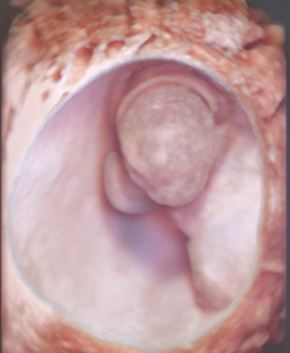

Nel campo dell’infertilità si eseguono le valutazioni della morfologia degli organi femminili in tridimensionale per la ricerca e la caratterizzazione di eventuali patologie intrauterine da inviare in isteroscopia, la ricerca di eventuali foci endometriosici che talora necessitano di ulteriori approfondimenti, la valutazione della pervietà tubarica attraverso la sonoisterosalpingografia con ausilio della metodica tridimensionale la cui accuratezza diagnostica ha dimostrato recentemente livelli molto alti rispetto alle metodiche tradizionali (isterosalpingografia) che espongono peraltro la paziente a radiazioni; il tutto in linea con le più recenti indicazioni delle più importanti Società Scientifiche.

foto 1: immagine di pervietà tubarica con sonoisterosalpingografia